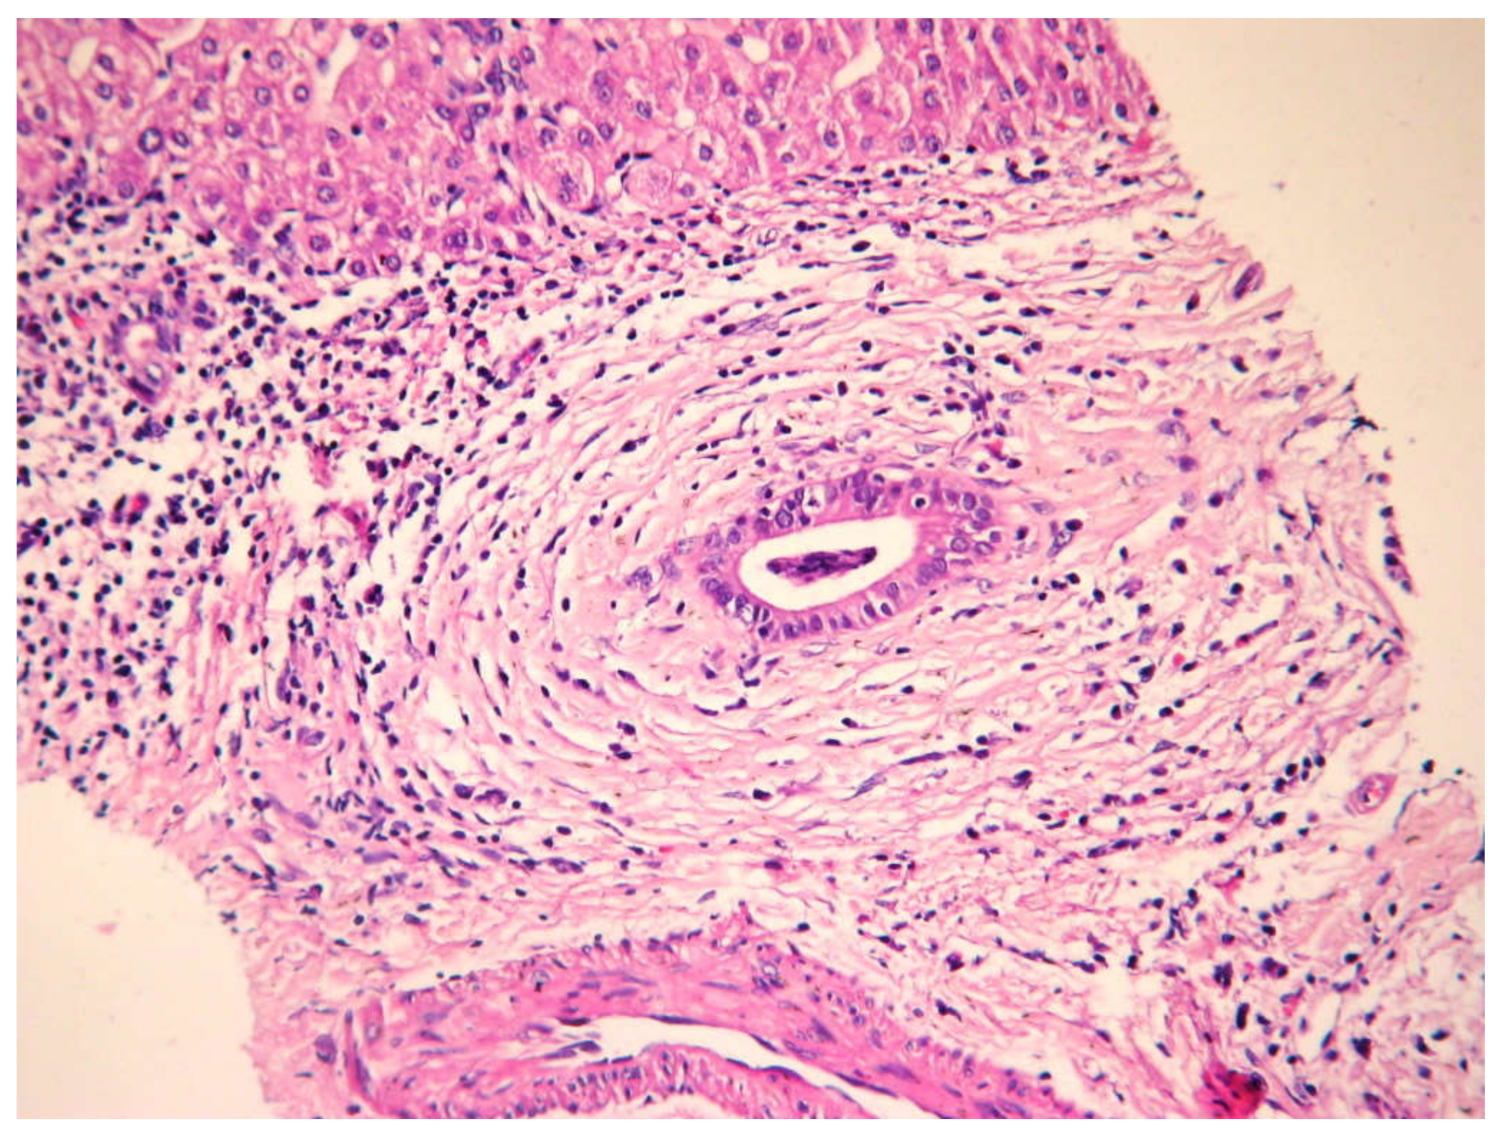

5.5. Histology